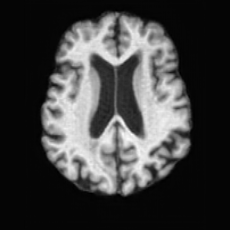

Conditional Generation. Fig. 4 (b) shows conditional generation results given a lesion mask. Conditioned on a single lesion mask, USB can generate an unlimited brain image samples that embed the specified lesion, producing diverse anatomical appearances while maintaining faithful pathological localization. As illustrated by the samples along each row, the generated pathological images exhibit variations in intensity, texture, and local tissue response.

In Tab. 1, we present the first quantitative benchmark evaluation of both generation tasks. For the unconditional generation task, we generated 256 paired lesion–brain samples for each lesion type (stroke and WMH). For the conditional generation task, we used masks from the ATLAS and ISLES test sets as stroke lesions, and masks from the ADNI test set as WMH lesions. Notably, for each lesion type, the unconditional generation achieved superior quantitative performance, highlighting that the paired diffusion mechanism effectively generates coherent lesion-brain pairs through joint modeling between USBbrain and USBlesion. Additional generation results are provided in Suppl. A.